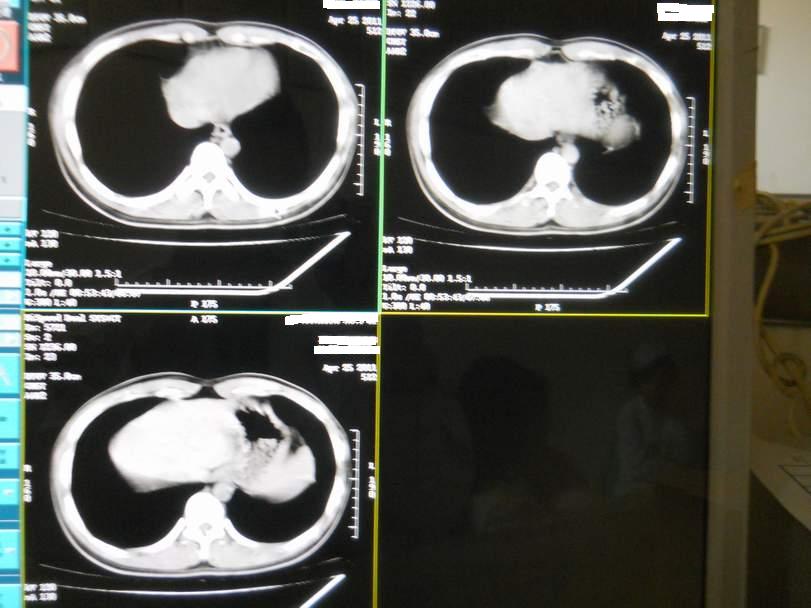

肺霉菌感染

男,22岁,一年前诊断马尔菲尼青霉菌感染,多次复查CT。多次HIV阴性。最近两次CT图片。有实验室结果。

最近实验室检查结果:霉菌感染。